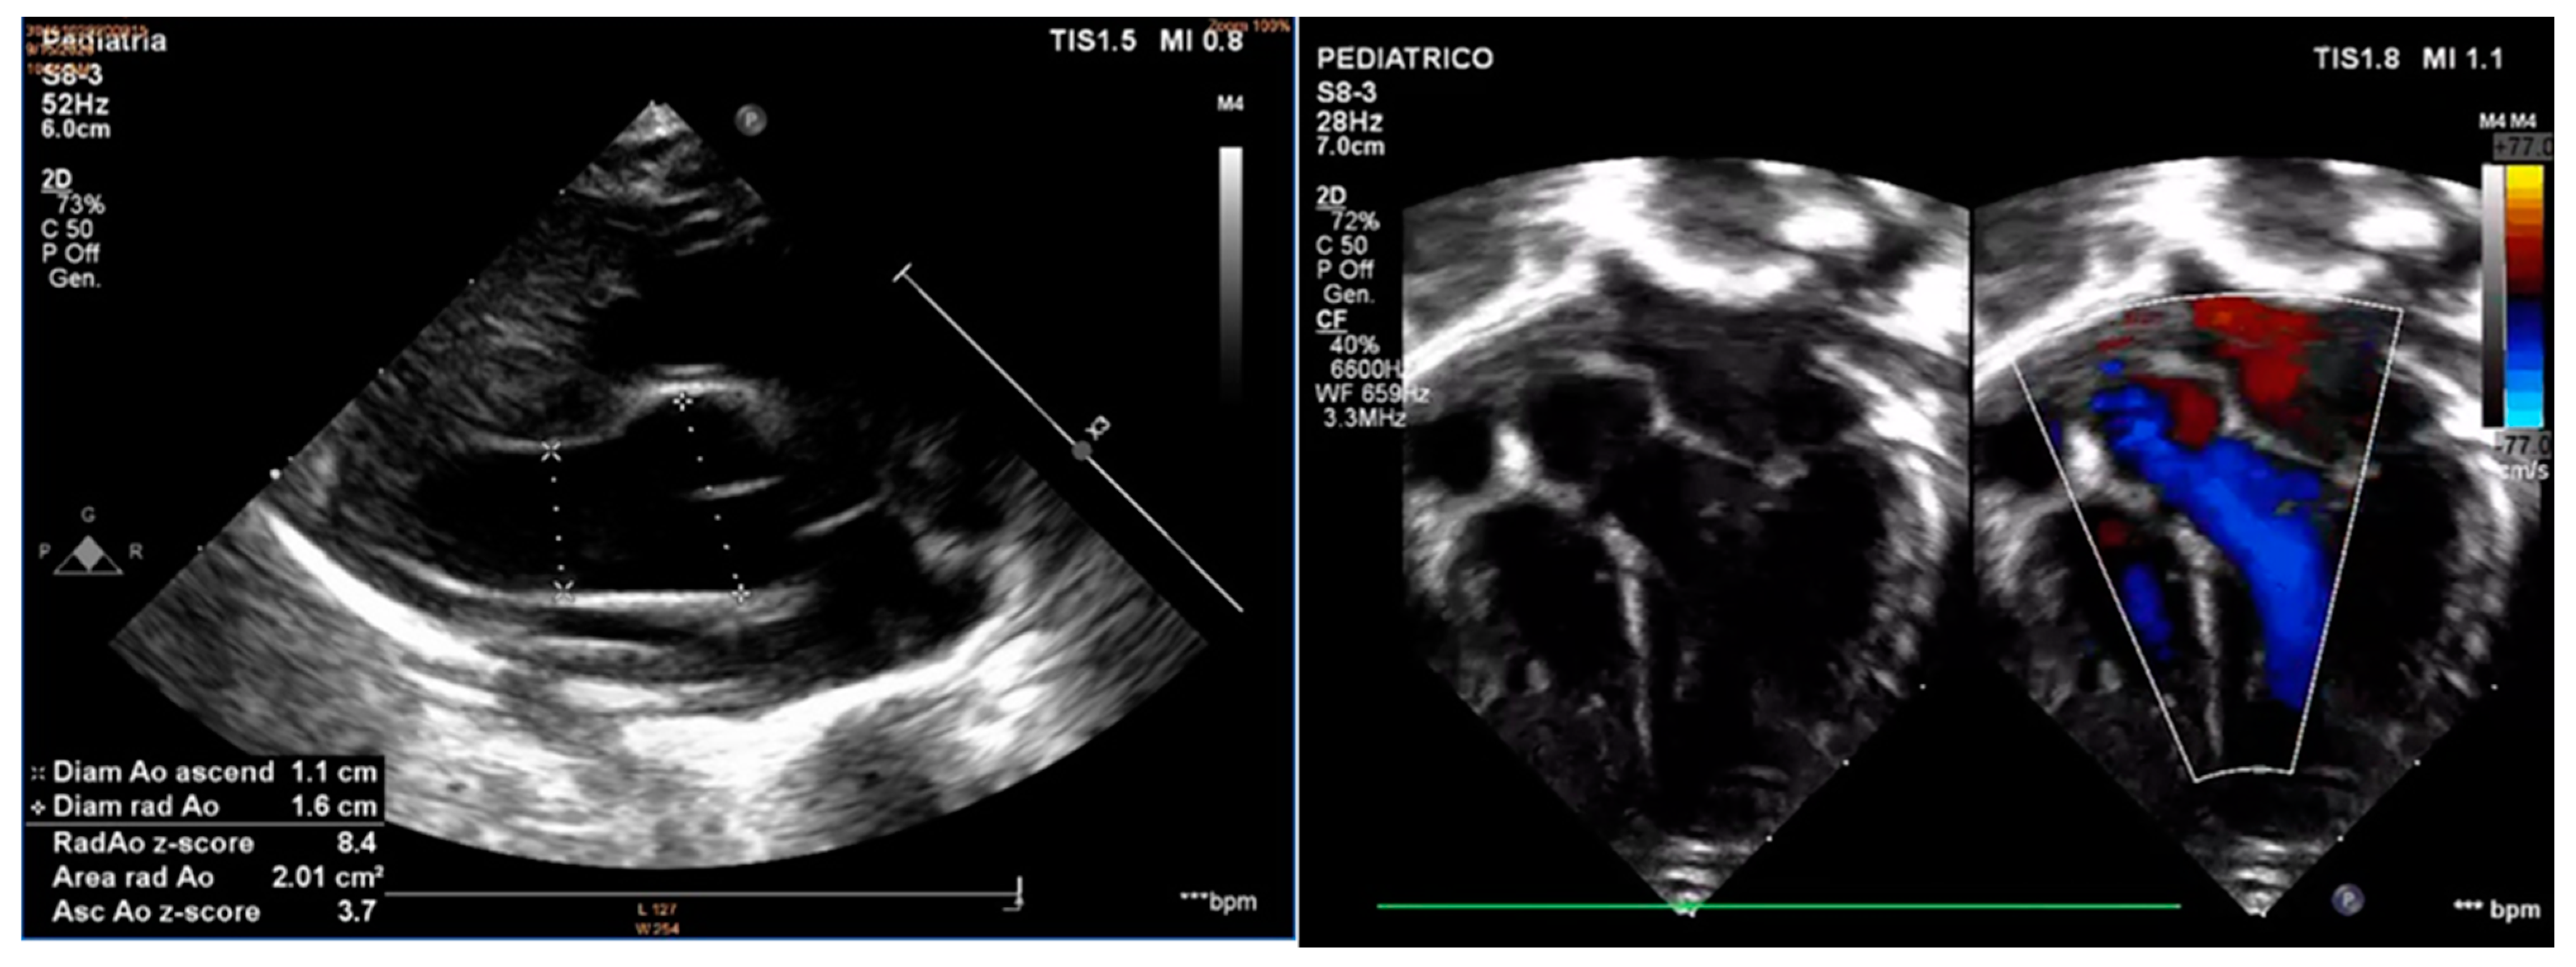

2. Case Report